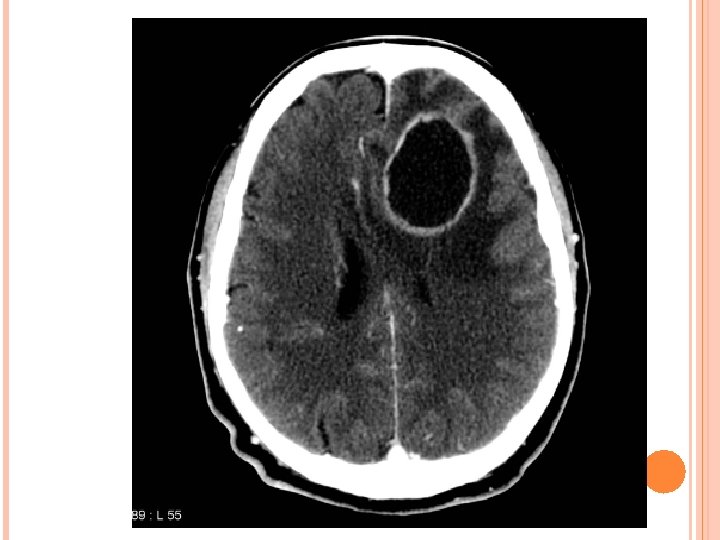

CT SCAN BRAIN WITH CONTRAST ( AFTER 1 WEEK)

SURGERY Aspiration thru burr hole (28 -6 -16) 15 ml pus aspirated Pus sent for culture and sensitivity.